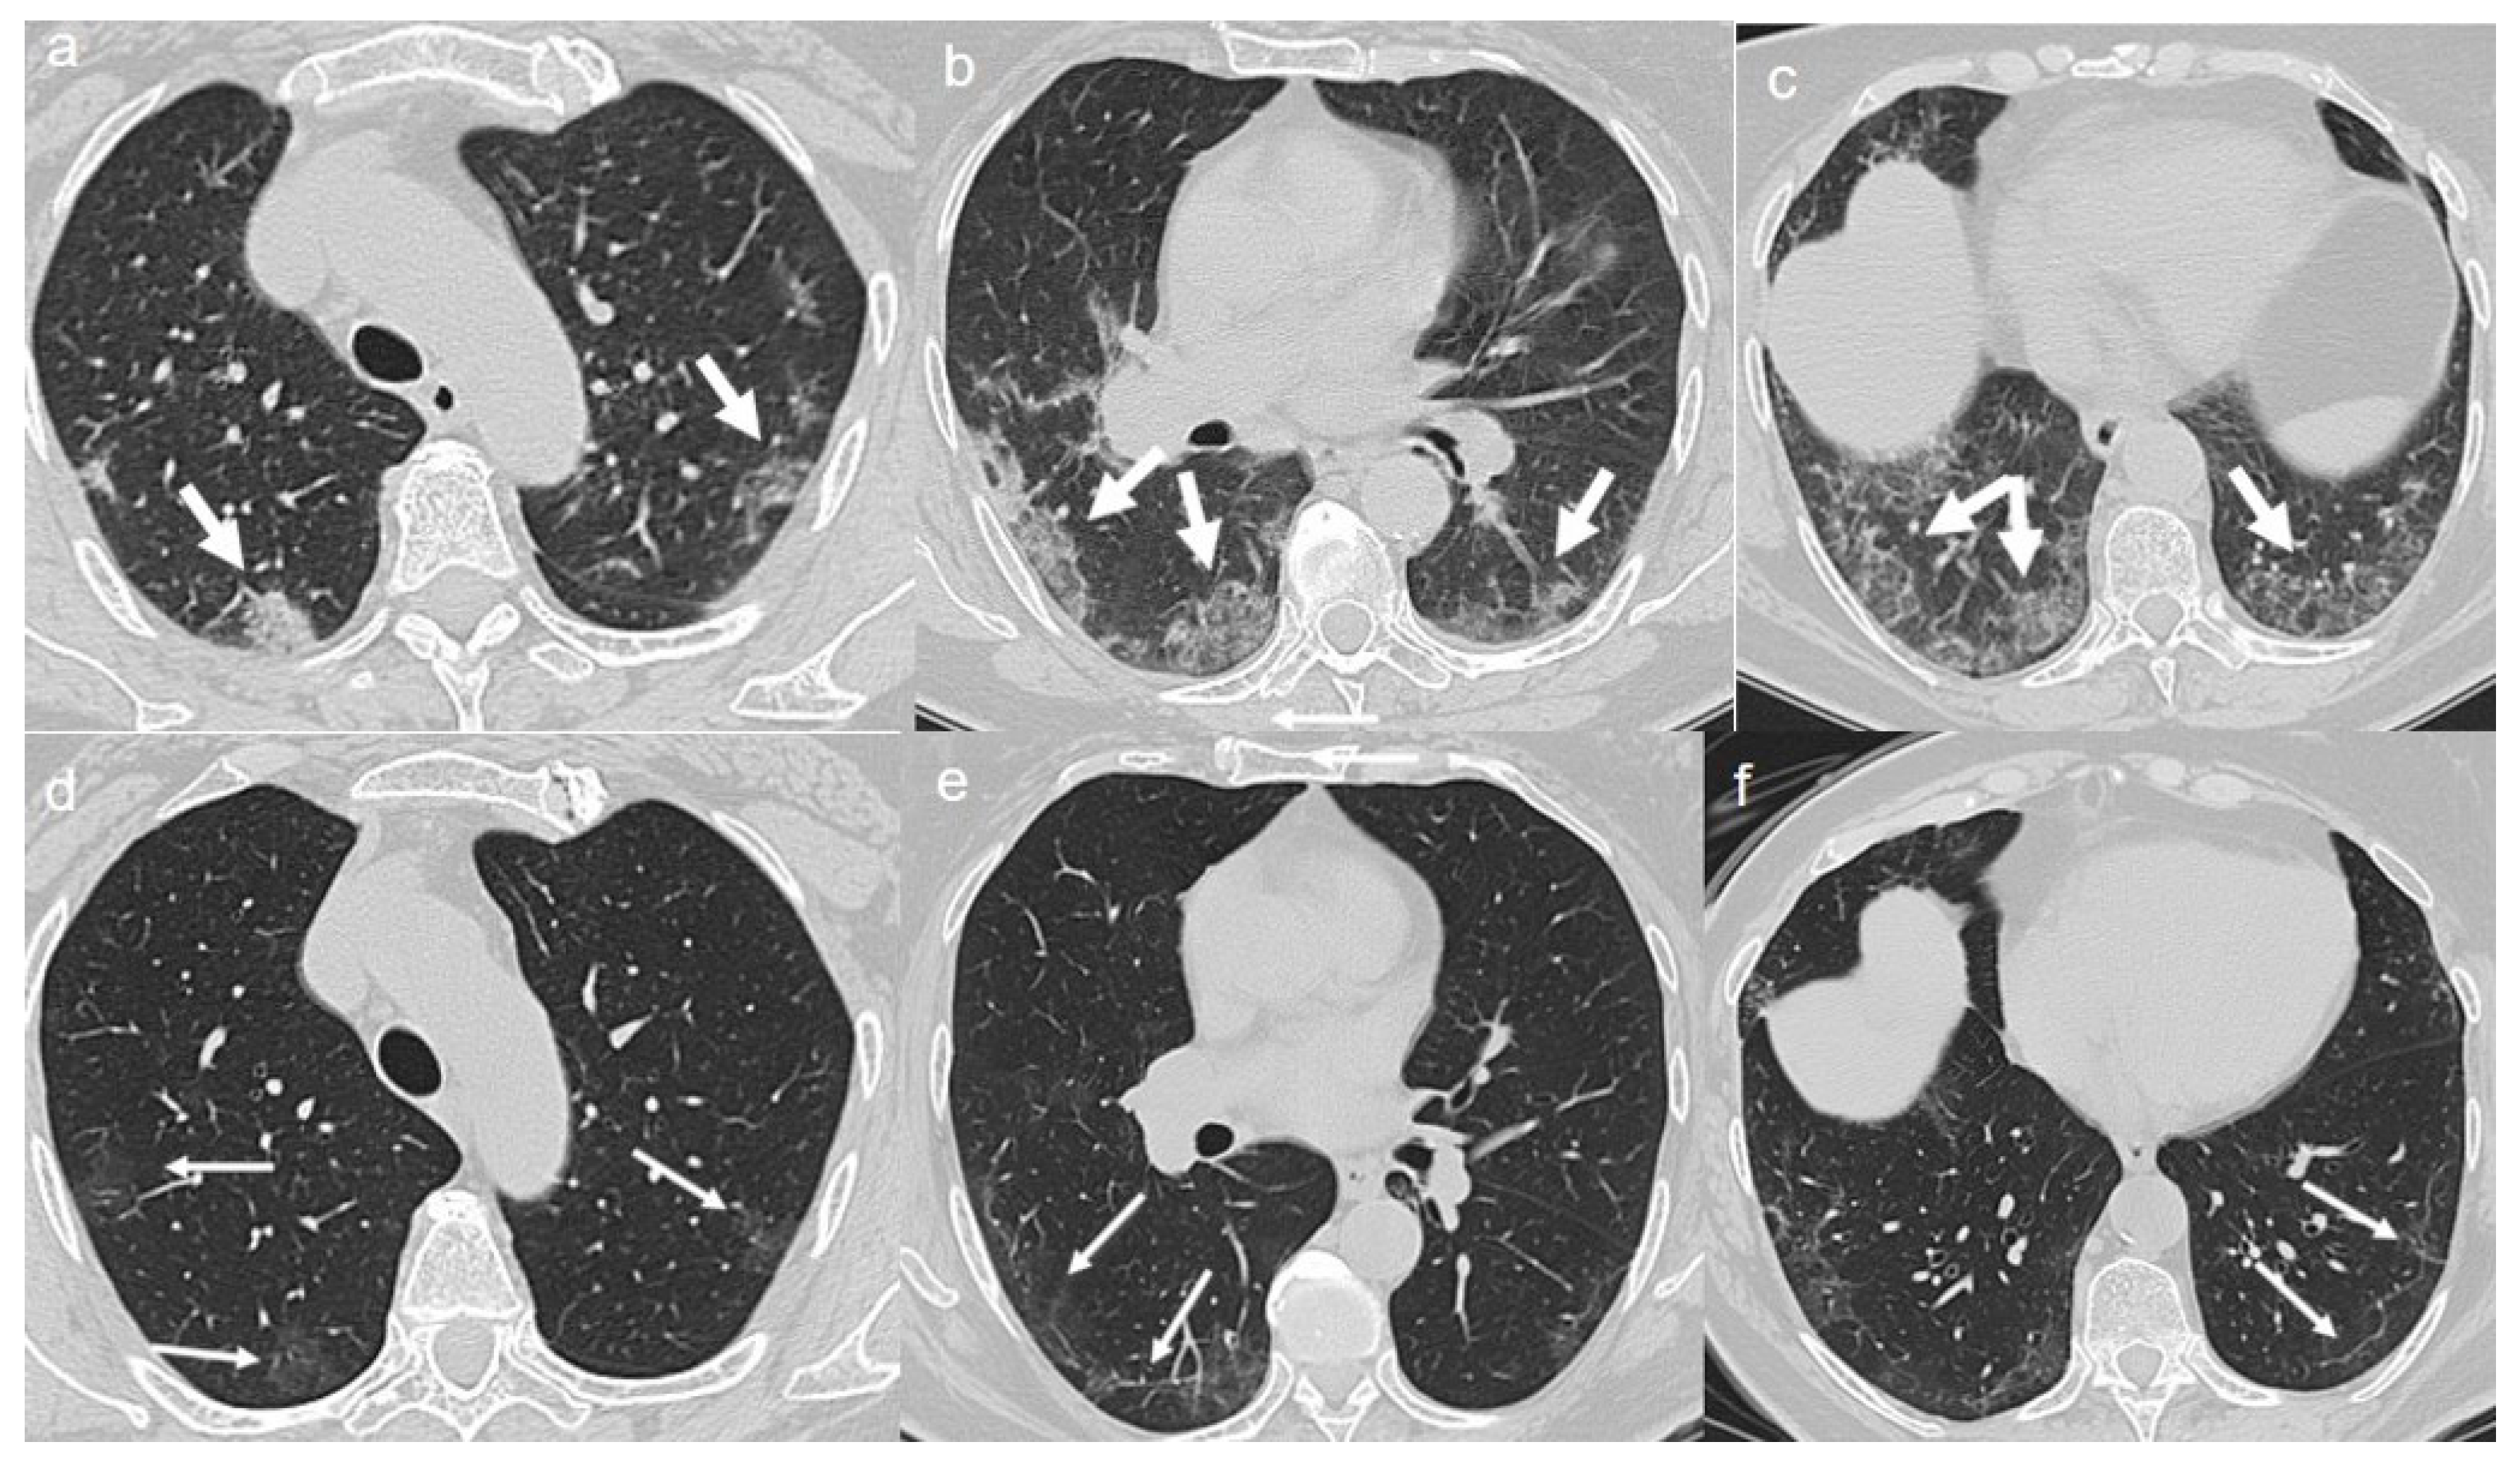

On admission, chest CT showed a diffuse “crazy paving pattern” peripherally located in the lower lobes (Figure 2a,b).

(a,b) CT shows a “crazy paving pattern” peripherally located in lower lobes (arrows). (c,d) CT after 4 months from the onset of symptoms shows bilateral persistence of mixed pattern characterized by GGOs (thin arrows in c) and fibrous streaks (thin arrows in d).

A chest CT at 4 months from the onset of symptoms showed the persistence of mixed pattern characterized by GGOs and fibrous streaks, bilaterally located. (Figure 2c,d).

On admission, chest CT showed a diffuse “crazy paving pattern” peripherally located in the upper and lower lobes (Figure 3a–c).

(a–c) CT shows a “crazy paving pattern” peripherally located in upper and lower lobes (arrows). (d–f) CT after 4 months from the onset of symptoms shows bilateral persistence of mixed pattern of GGOs (thin arrows in d) and fibrous streaks (thin arrows in e,f).

A CT at 4 months from the onset of symptoms revealed the bilateral persistence of a mixed pattern characterized by GGOs and fibrous streaks (Figure 3d–f).